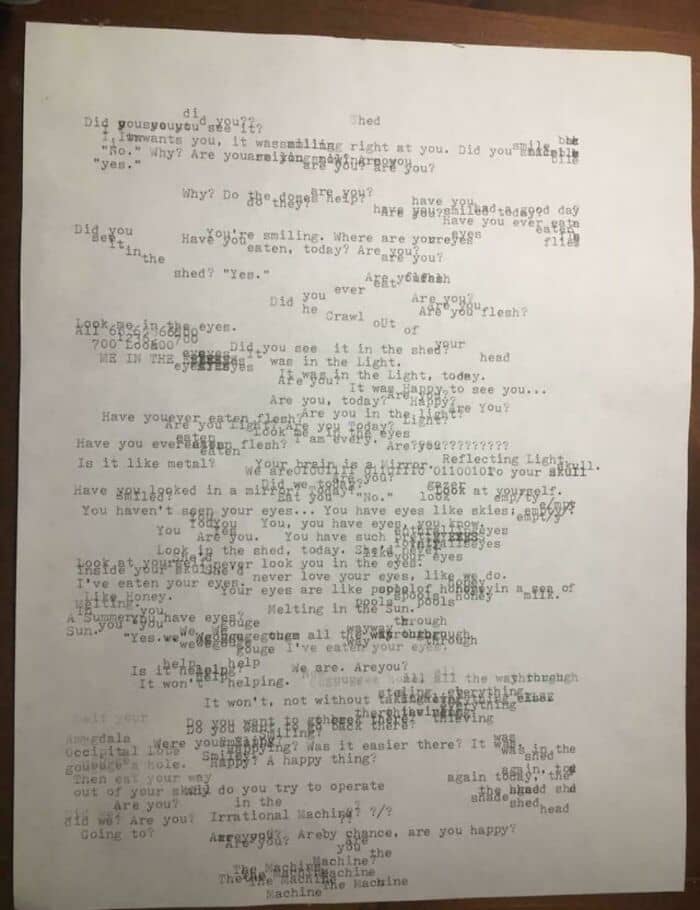

#18 Schizophrenic Person Uses Typewriter To Visualize The Voices They Hear